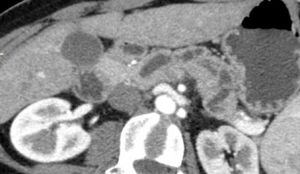

Lesione non visibile all’imaging. Dilatazione del dotto pancreatico principale all’esame TC con stop in regione istmica in assenza di lesioni focali.